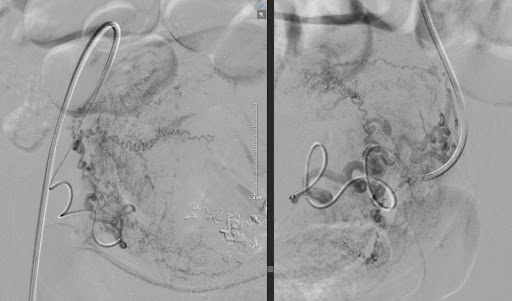

Thủ thuật được thực hiện trong phòng can thiệp mạch với hệ thống chụp mạch số hóa xóa nền (DSA).

1. Bác sĩ đưa một ống thông nhỏ vào động mạch (thường qua động mạch đùi hoặc động mạch quay).

2. Dưới hướng dẫn của hệ thống chụp mạch, ống thông được đưa đến động mạch tử cung.

3. Các hạt gây tắc mạch được bơm vào nhằm làm giảm dòng máu nuôi các tổn thương lạc nội mạc tử cung.